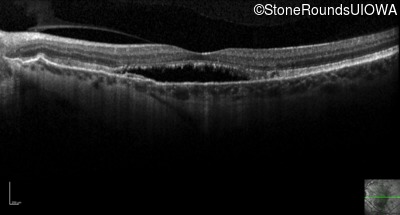

Optical Coherence Tomography - Left - 20/30 -2 sc

Exemplar / OCT Stack